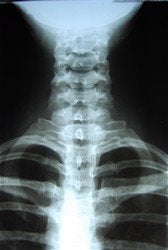

Digital X-ray

X-rays are often taken on most patients to give the doctor an inside look at what is going on with the bone structure of the entire spine and surrounding skeletal structure. From this x-ray, the doctor can tell your current spine angles as well as any potential further issues including the potential for additional information such as an MRI.